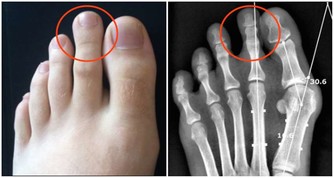

手腳麻木

有些人會感到手指變得不靈活,有些人會感到腳指頭麻木,還有些人會感覺到脖子和背部肌肉緊張、酸痛等,這些症狀往往表現在重度高血壓患者身上,一般情況下,當血壓降低時,這些症狀也會有所好轉。

另外,如果這種肢體麻木的現像一直不消失,而且每次出現麻木的時間都比較長,或者固定出現於某一肢體部位,並且伴有肢體乏力、抽筋、跳痛時,大家一定要引起高度重視,因為這種情況很容易誘發中風。